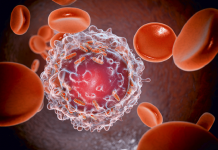

هوى الشام|يغفل عدد كبير من الناس مسألة الاهتمام بصحة قلبهم، وذلك بسبب نمط الحياة المعاصر، الأمر الذي يساهم في ارتفاع عدد مرضى القلب بشكل سنوي.

وتعد أمراض القلب المتنوعة مسؤولة عن ثلث الوفيات في مختلف أنحاء العالم، وفق جمعية القلب الأميركية.

وقال موقع “هيلث لاين” إنه يمكن للإنسان العادي أن يطرح على نفسه بعض الأسئلة السهلة والبسيطة ليعرف مدى صحة قلبه.

ومن الأسئلة المهمة المرتبطة بصحة قلب الإنسان، تلك المتعلقة بالنظام الغذائي وبنمط حياتك اليومي.

ويطرح الطبيب على مرضى القلب هذه الأسئلة: هل تتناول الكثير من الخضراوات والفواكه؟ هل تتناول الكثير من الدهون المشبعة؟ هل تتناول الكثير من الملح؟ هل تمارس الرياضة بشكل يومي؟ هل تعاني الإجهاد والضغط؟ هل تدخن كثيرا؟ هل تشرب الكحول بصفة دورية؟ هل لديك تاريخ عائلي مع أمراض القلب؟

ويعد إدمان التدخين وكثرة الإجهاد وقلة ممارسة الرياضة من العوامل التي تساهم بارتفاع مخاطر الإصابة بأحد أمراض القلب.